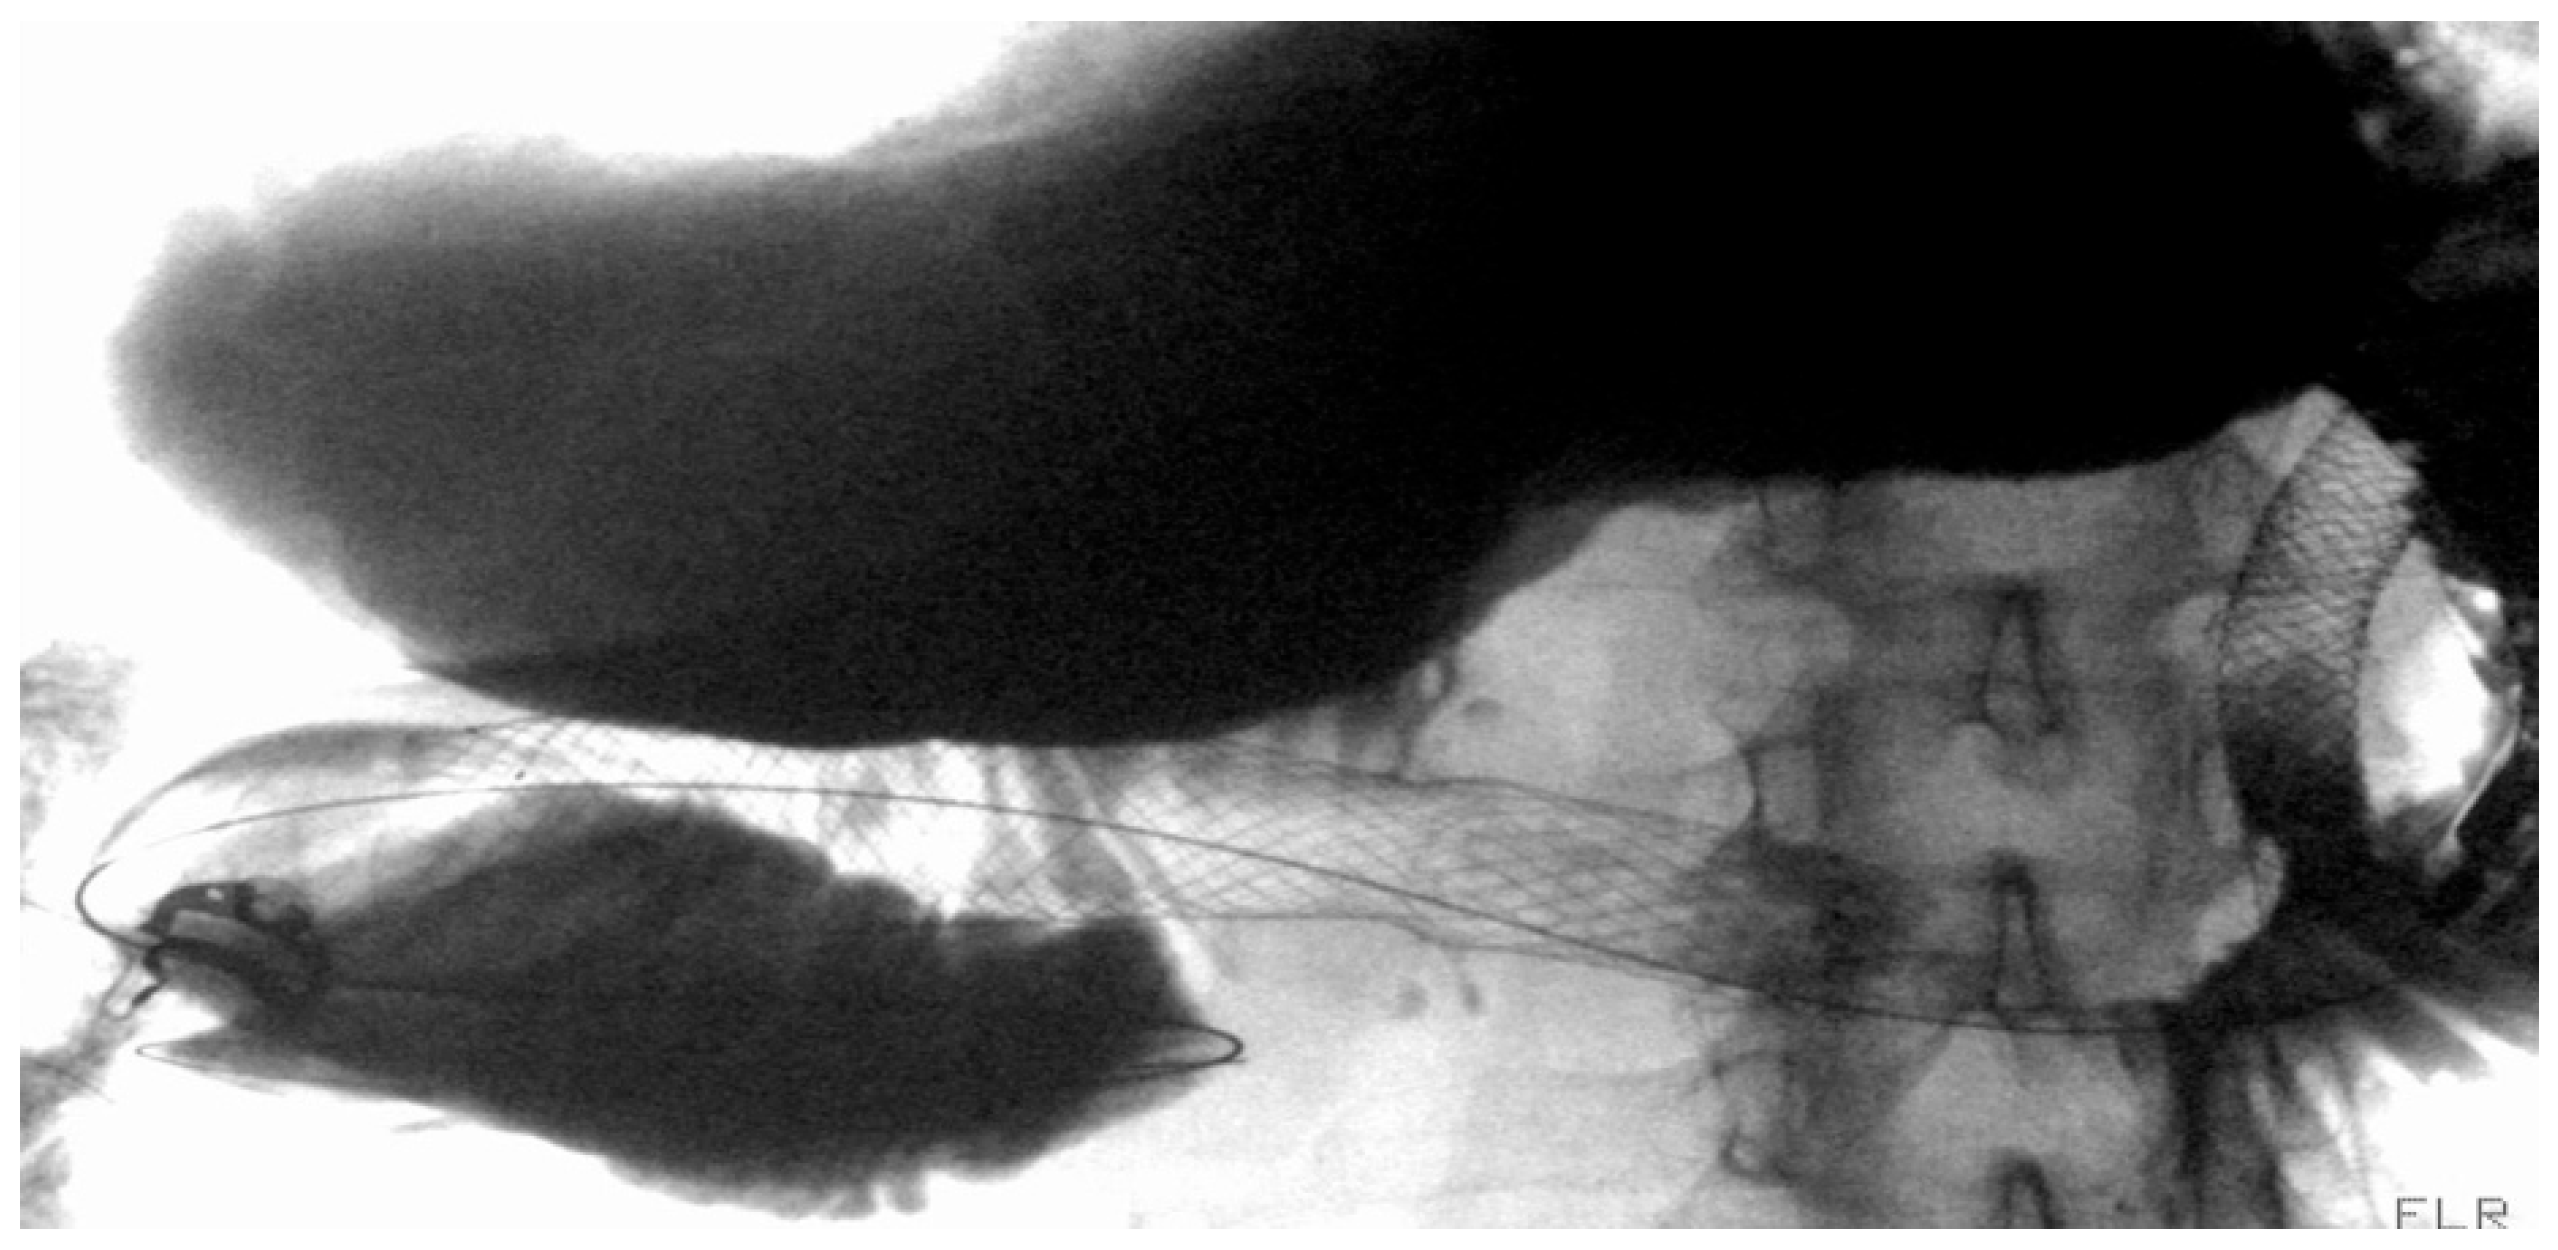

3.4. Esophageal Acute Variceal Bleeding

3.4.1. Role of Stent

Indication and Mechanism of Action

Efficacy and Adverse Events